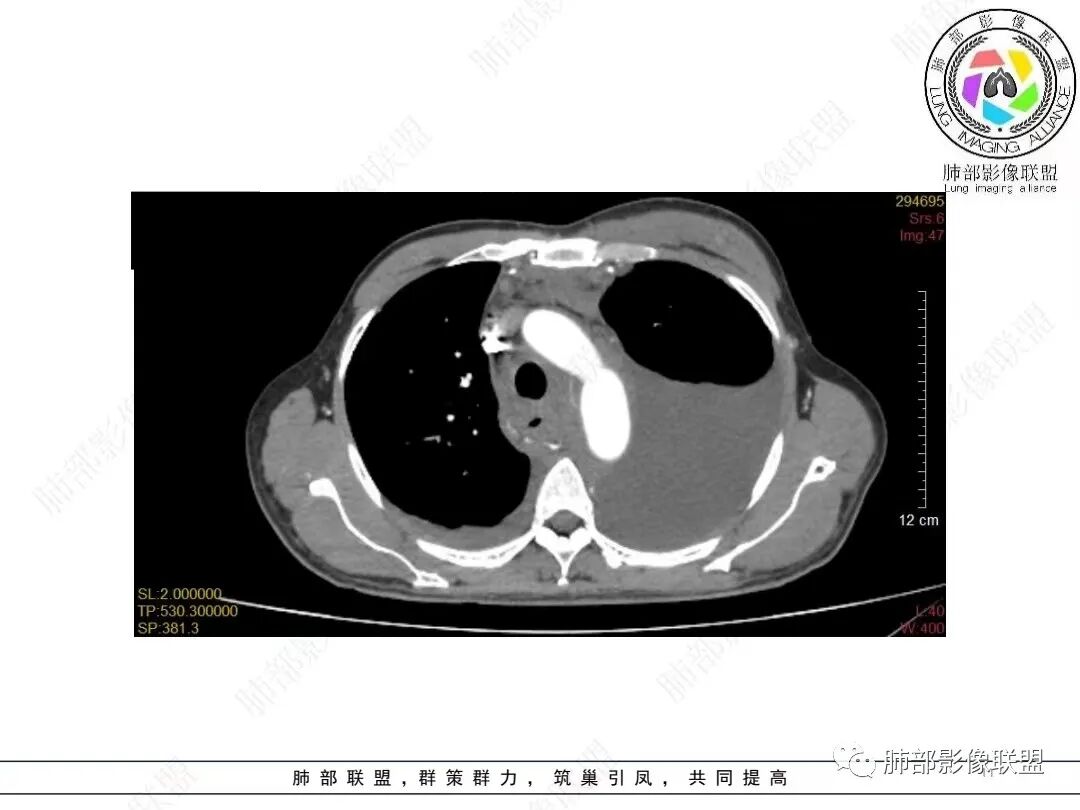

男,52,胸闷、气短、咳嗽1月。长期吸烟,NSE、细胞角蛋白19片段增高。胸部CT:甲状腺右叶结节,增强可见多发低密度区。纵隔、肺门多发淋巴结肿大融合,周围脂肪间隙消失,冰冻纵隔;针孔状食管;两侧胸腔积液伴肺不张,左侧重,胸水清澈。考虑恶性,SCLC?鉴别淋巴瘤、转移瘤等。

左侧锁骨上下及纵膈多发淋巴结肿大,左侧胸膜呈环周型增厚,左侧胸腔大量积液半肺不张,右侧胸腔少量积液,甲状腺右叶结节,中年男性,胸闷气短咳嗽,长期吸烟,NSE、细胞角蛋白19片段增高。考虑恶性,小细胞肺癌,鉴别淋巴瘤

目前的图:主要是胸部的病灶。胸膜弥漫斑块状增厚。强化明显,内部血管漂浮。前纵隔部分病灶强化偏低。

累及多个腔隙、特别是后纵隔、胸膜为主

说实话,我个人认为前纵隔的更符合增生的胸腺,或者胸腺边缘受侵犯而已。因为其内很多脂肪间隔,提示病灶是多发中心。单一的按理不应该有脂肪间隙。其次其 强化明显低于其他病灶。所以我认为胸腺主要是增生为主。

2.影像学特点:病变范围相当广泛,多发块状影累及纵隔、胸膜、前胸壁(胸大肌下)、前上腹壁等。胸膜弥漫性斑状增厚为主,明显强化,纵隔旁椭圆形块影较密实,沿胸膜分布趋势,未见支气管等结构进入。后纵隔块影较大,占位效应明显,肺静脉受累狭窄。双侧胸腔积液。